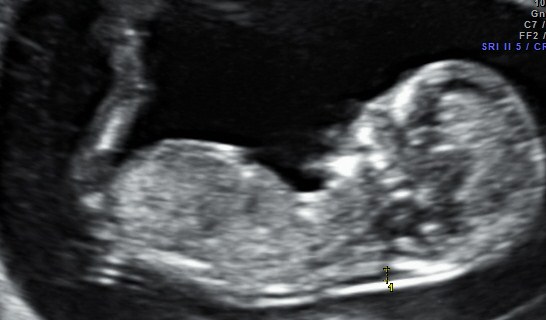

I would love your thoughts on my 11w6d scan. I have read lots about the nub theory and thought I'd be able to guess for sure - and I do think it's a good scan pic - but is it slightly angled up or straight?! And there's a strange fork at the inside end? I can't follow the spine enough to work it out, so would love your thoughts.

If it is the nub im seeing im leaning boy as it looks like it already angled a bit x

I *think* that MAYBE I see a boy nub, but I'm thinking more likely I don't see a nub at all... sorry :(

I don't see a nub... But I absolutley love the legs in this pic

The leg is blocking the nub so 50/50.

Thanks so far girls. I must have it so so wrong as I thought that was a clear nub - the darkest line just below where you see the legs start! Silly me!

Does this other scan pic reveal anything? Or the skull? Thank you :)